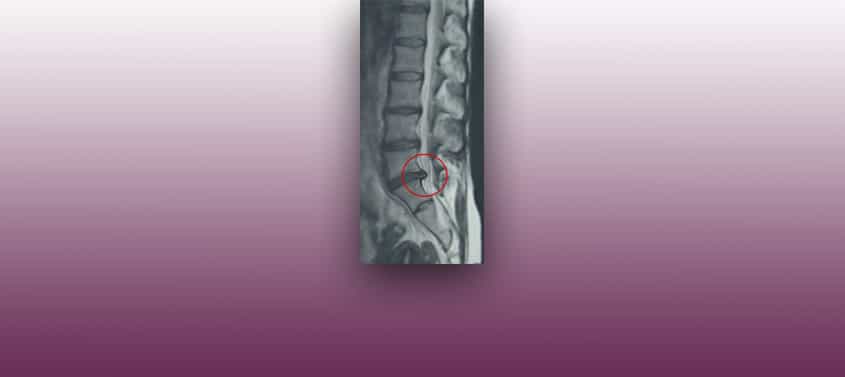

فتق الأقراص القطنية (الإنزلاق الغضروفي القطني)

.في المنشور ” فتق الأقراص القطنية في مكان العمل […]”، يتم قياس و مقارنة نتائجنا مع منشورات أخرى مماثلة، حاصلين على فارق كبير لصالح تقنياتنا الجراحية لمعالجة فتق الأقراص القطنية أو مايسمى بداء القرص التنكسي :التدخل الجراحي الأكثر شيوعا هو داء القرص التنكسي في الفقرات القطنية. و في مايتعلق بذلك المرضى يسألون هل سأشفى من هذا […]